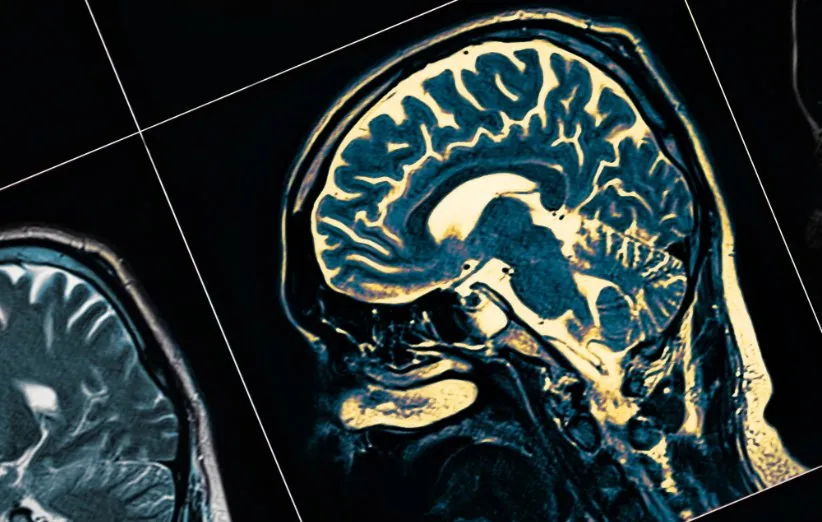

البته لازم به ذکر است که بخشی از مغز به نام هیپوکامپ (Hippocampus)، که تا حد زیادی مسئول حافظه است، در دوره نوزادی به طور کامل رشد نکرده است.

توضیح احتمالی دیگر برای نبود حافظه خودزندگینامهای این است که چون نوزادان تا اواخر سال دوم زندگی توانایی سخن گفتن ندارند، نمیتوانند روایتهایی از زندگی خود بسازند که بعداً بتوانند به خاطر بیاورند و برای دیگران تعریف کنند. در نهایت، باید بدانید که هیپوکامپ (Hippocampus)، که تا حد زیادی مسئول حافظه در مغز است، در دوره نوزادی به طور کامل رشد نمیکند. بنابراین دانشمندان به بررسی این موضوع ادامه خواهند داد تا این حدسهای مختلف را بررسی کنند و به این نتیجه برسند که چرا شما نمیتوانید چیزهای زیادی از زندگی قبل از 2 سالگی خود به خاطر بیاورید.